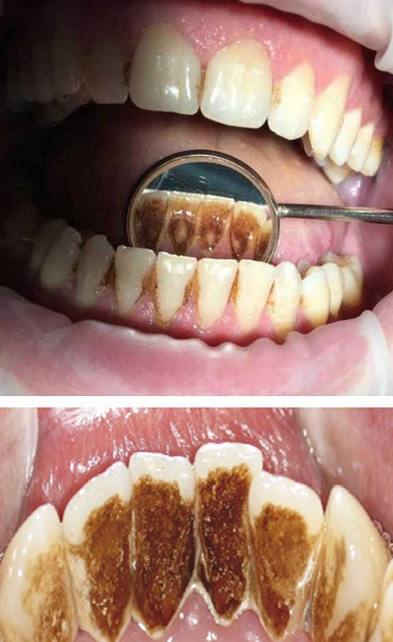

Профессиональная гигиена особенно важна при ортодонтическом лечении, ведь в повседневной жизни, дома, очень сложно поддерживать должный уровень гигиены полости рта! Даже если вы используете ирригатор и специальные ёршики! В нашей рубрике «до/после» вы видите то, что может быть с зубами при лечении брекетами, если не проводить своевременную чистку у врача-стоматолога. Марухно Дарья Александровна провела профессиональную чистку в несколько этапов, чтобы вернуть пациентке белизну ее собственных зубов! Брекет-система была поставлена не в нашей клинике, и почему пациентка не обратилась за профессиональной помощью раньше-вопрос) Но в данном случае, главное – итог! Кровоточивость после даже обычной чистки в такой клинической ситуации – естественный результат. Ведь обильный зубной налёт и зубной камень вызывают воспаление дёсен в виде гингивита, а порой даже пародонтита.

Доктор: Марухно Дарья Александровна